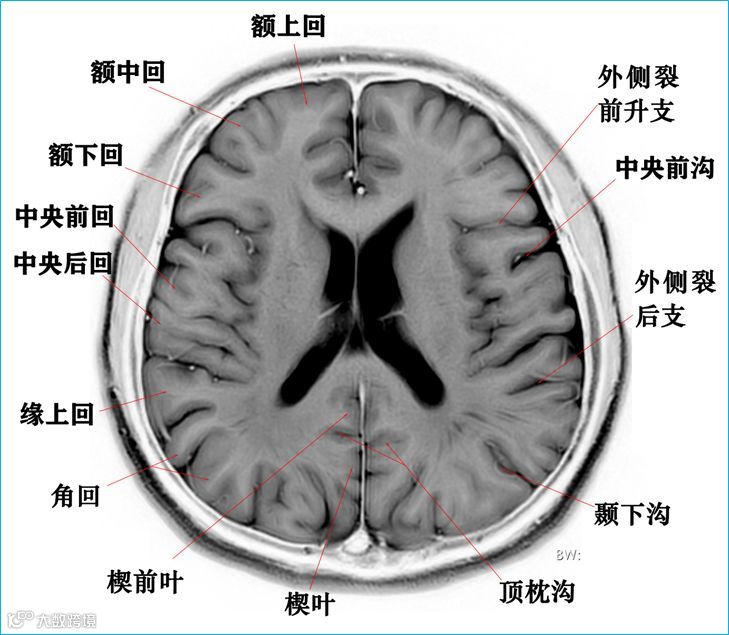

在T2WI反相图学下的颅脑断层解剖(吴晓安老师亲自手动标准)以及标本断层解剖,满满干货,坐在小板凳上,一起学习吧……